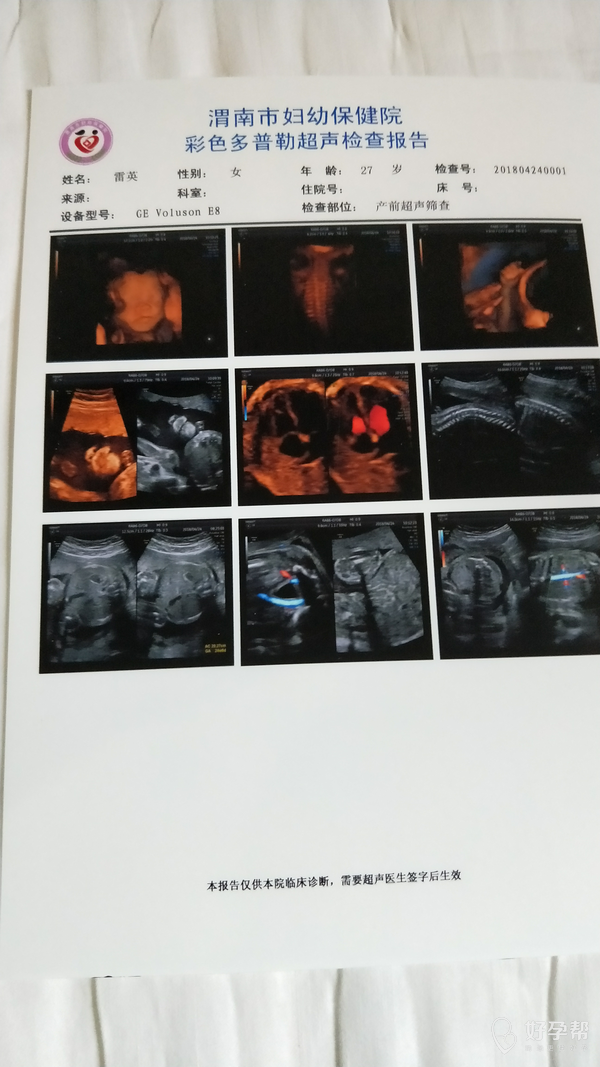

试管婴儿怀孕24周加1天

建议您28周复查彩超,32周再复查